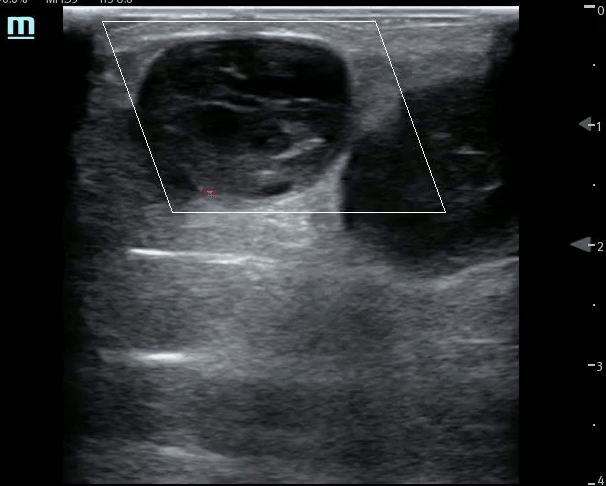

Mid Ureter Obstructing Stone